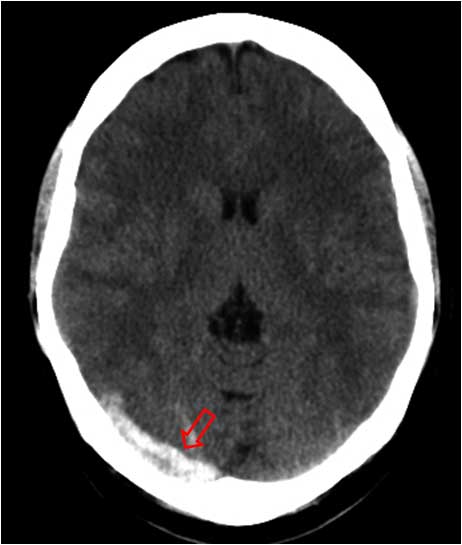

SIGNO DE LA CUERDA

Es un signo visible en la TC craneal sin contraste y que corresponde a pequeñas venas corticales trombosadas. Es un hallazgo poco frecuente consistente en una imagen lineal densa sinuosa que ocupa un surco de la convexidad (flecha), que puede confundirse con hemorragia subaracnoidea. Se observa además una pequeña zona hiperdensa en el lóbulo parietal derecho correspondiente a un infarto venoso hemorrágico.